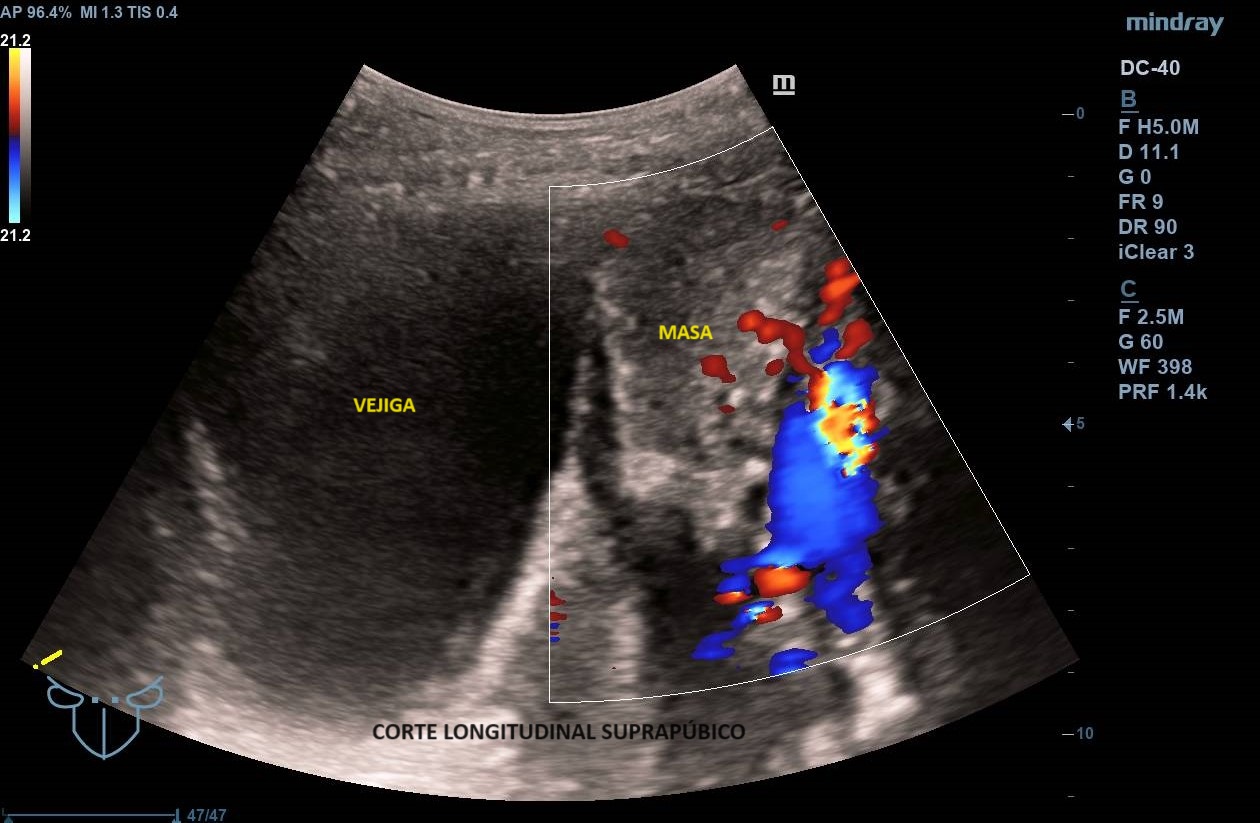

Ecografía abdominal clínica: Masa heterogénea que ocupa todo el abdomen, de aspecto sólido, vascularizada con zonas hipoecoicas-anecoicas en su interior. Riñones con eco-estructura sin alteraciones, hígado sin LOES. Vejiga sin engrosamiento de paredes, útero parcialmente visible. Anejos y retroperitoneo no valorables. No líquido libre.

Los leiomiomas uterinos son el tumor más frecuente de pelvis en la mujer. La ecografía es la primera línea de estudio. Habitualmente s

e describen como masas bien delimitadas redondeadas hipoecoicas con sombra acústica, aunque también pueden tener áreas isoecoicas e hiperecoicas. Pueden presentar necrosis central (áreas anecoicas) o calcificaciones, sin implicar malignización. El Doppler-color suele mostrar una distribución irregular de los vasos. El diagnóstico definitivo es el anatomo-patológico.